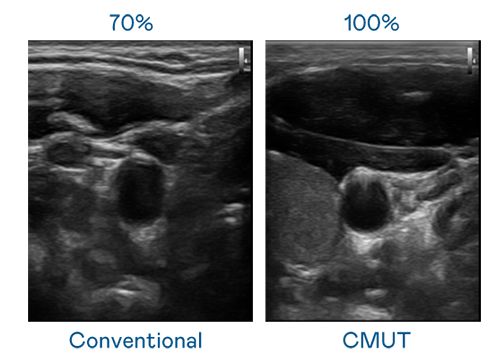

CMUT 技术是一种用电容式微机电元件来产生超音波讯号的技术。与传统 PZT 压电式技术相比,CMUT 频宽增加 30%,更宽频的超音波讯号让影像解析度大幅提升,是实现高影像品质医疗超音波扫描、促进精准医疗发展的关键技术。

超音波影像的解析度高低,首先取决于探头能发出的讯号频宽。pg电子 CMUT 可提供高清晰的超音波讯号,提供高频宽、高灵敏度、影像纹理细节更高的超音波影像,协助医护人员缩短影像判读时间及利用精准的医疗影像进行诊断。